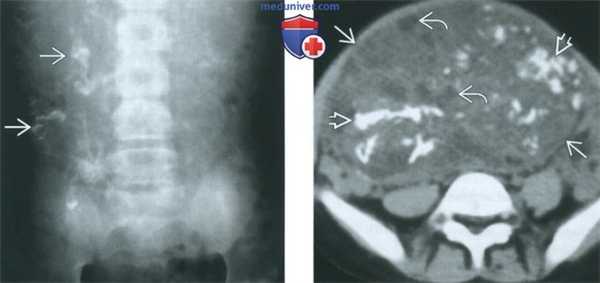

(Слева) При обзорной рентгенографии органов брюшной полости и таза в переднезадней проекции у 5-месячной девочки выявляются рассеянные очаги обызвествления неправильной формы.

(Справа) При нативной КТ в аксиальной плоскости у этой же девочки визуализируется преимущественно солидная опухоль таза, видны пласты обызвествленной ткани Н и кистозные изменения.